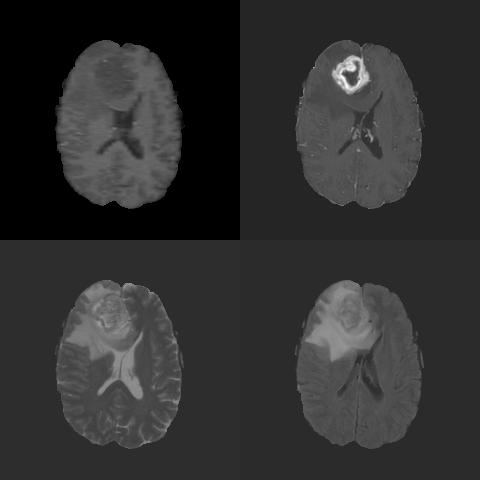

We used the Brain Tumor Image Segmentation Challenge (BRATS)[16] to evaluate performance of the proposed approach. The 2015 BRATS data set consists of 274 samples: 220 patients with high-grade GBM (HGG) and 54 with low-grade GBM (LGG). Each patient has 4 modalities (T1 post-contrast, T1 pre-contrast, T2-weighted, and FLAIR) and an expert segmentation that we treat as ground truth. The expert segmentation, which provides pixel-wise labeling into five segmentations based on the consensus of eleven radiologists: 0=non-tumor0non-tumor0=\text{non-tumor}, 1=necrosis1necrosis1=\text{necrosis}, 2=edema2edema2=\text{edema}, 3=non-enhancing3non-enhancing3=\text{non-enhancing}, and 4=enhancing4enhancing4=\text{enhancing}. We additionally included BRATS 2013 dataset to compare with prior studies. All images were pre-processed by stripping the skull, co-registering images, and interpolating images to 240×240×155240240155240\times 240\times 155 pixels (Figure 2).

Refer to caption

(a) Modalities

(b) Labels

Figure 2: BRATS image data. (a) The four imaging modalities (upper left: T1-Pre, upper right: T1-Post, lower left: T2W, lower right: FLAIR). (b) The four subregions (yellow: necrosis, green: edema, blue: non-enhancing, purple: enhancing), corresponding to the scans in (a). (c) A visualization of the labels superimposed on each modality.